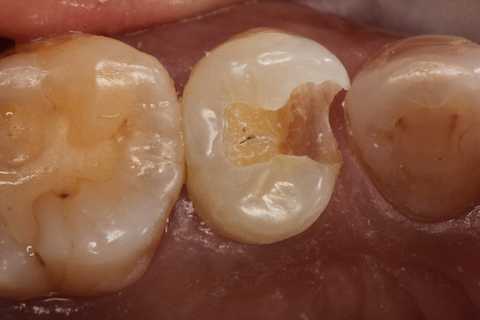

40代女性、左上5、冷水痛+

注意点はCRの接着面は新鮮歯質を確保して歯髄に近いところの軟化象牙質はあまり追求しないでも良い。α-TCPセメントの硬化と接着を妨げない程度に乾燥できれば良い。軟化象牙質は原材料のα-TCPと多少の水分があれば自然に再硬化するようだ。

この症例はストリップスを使っていない。使わない方が確実に充填できると思う。

では時系列でどうぞ